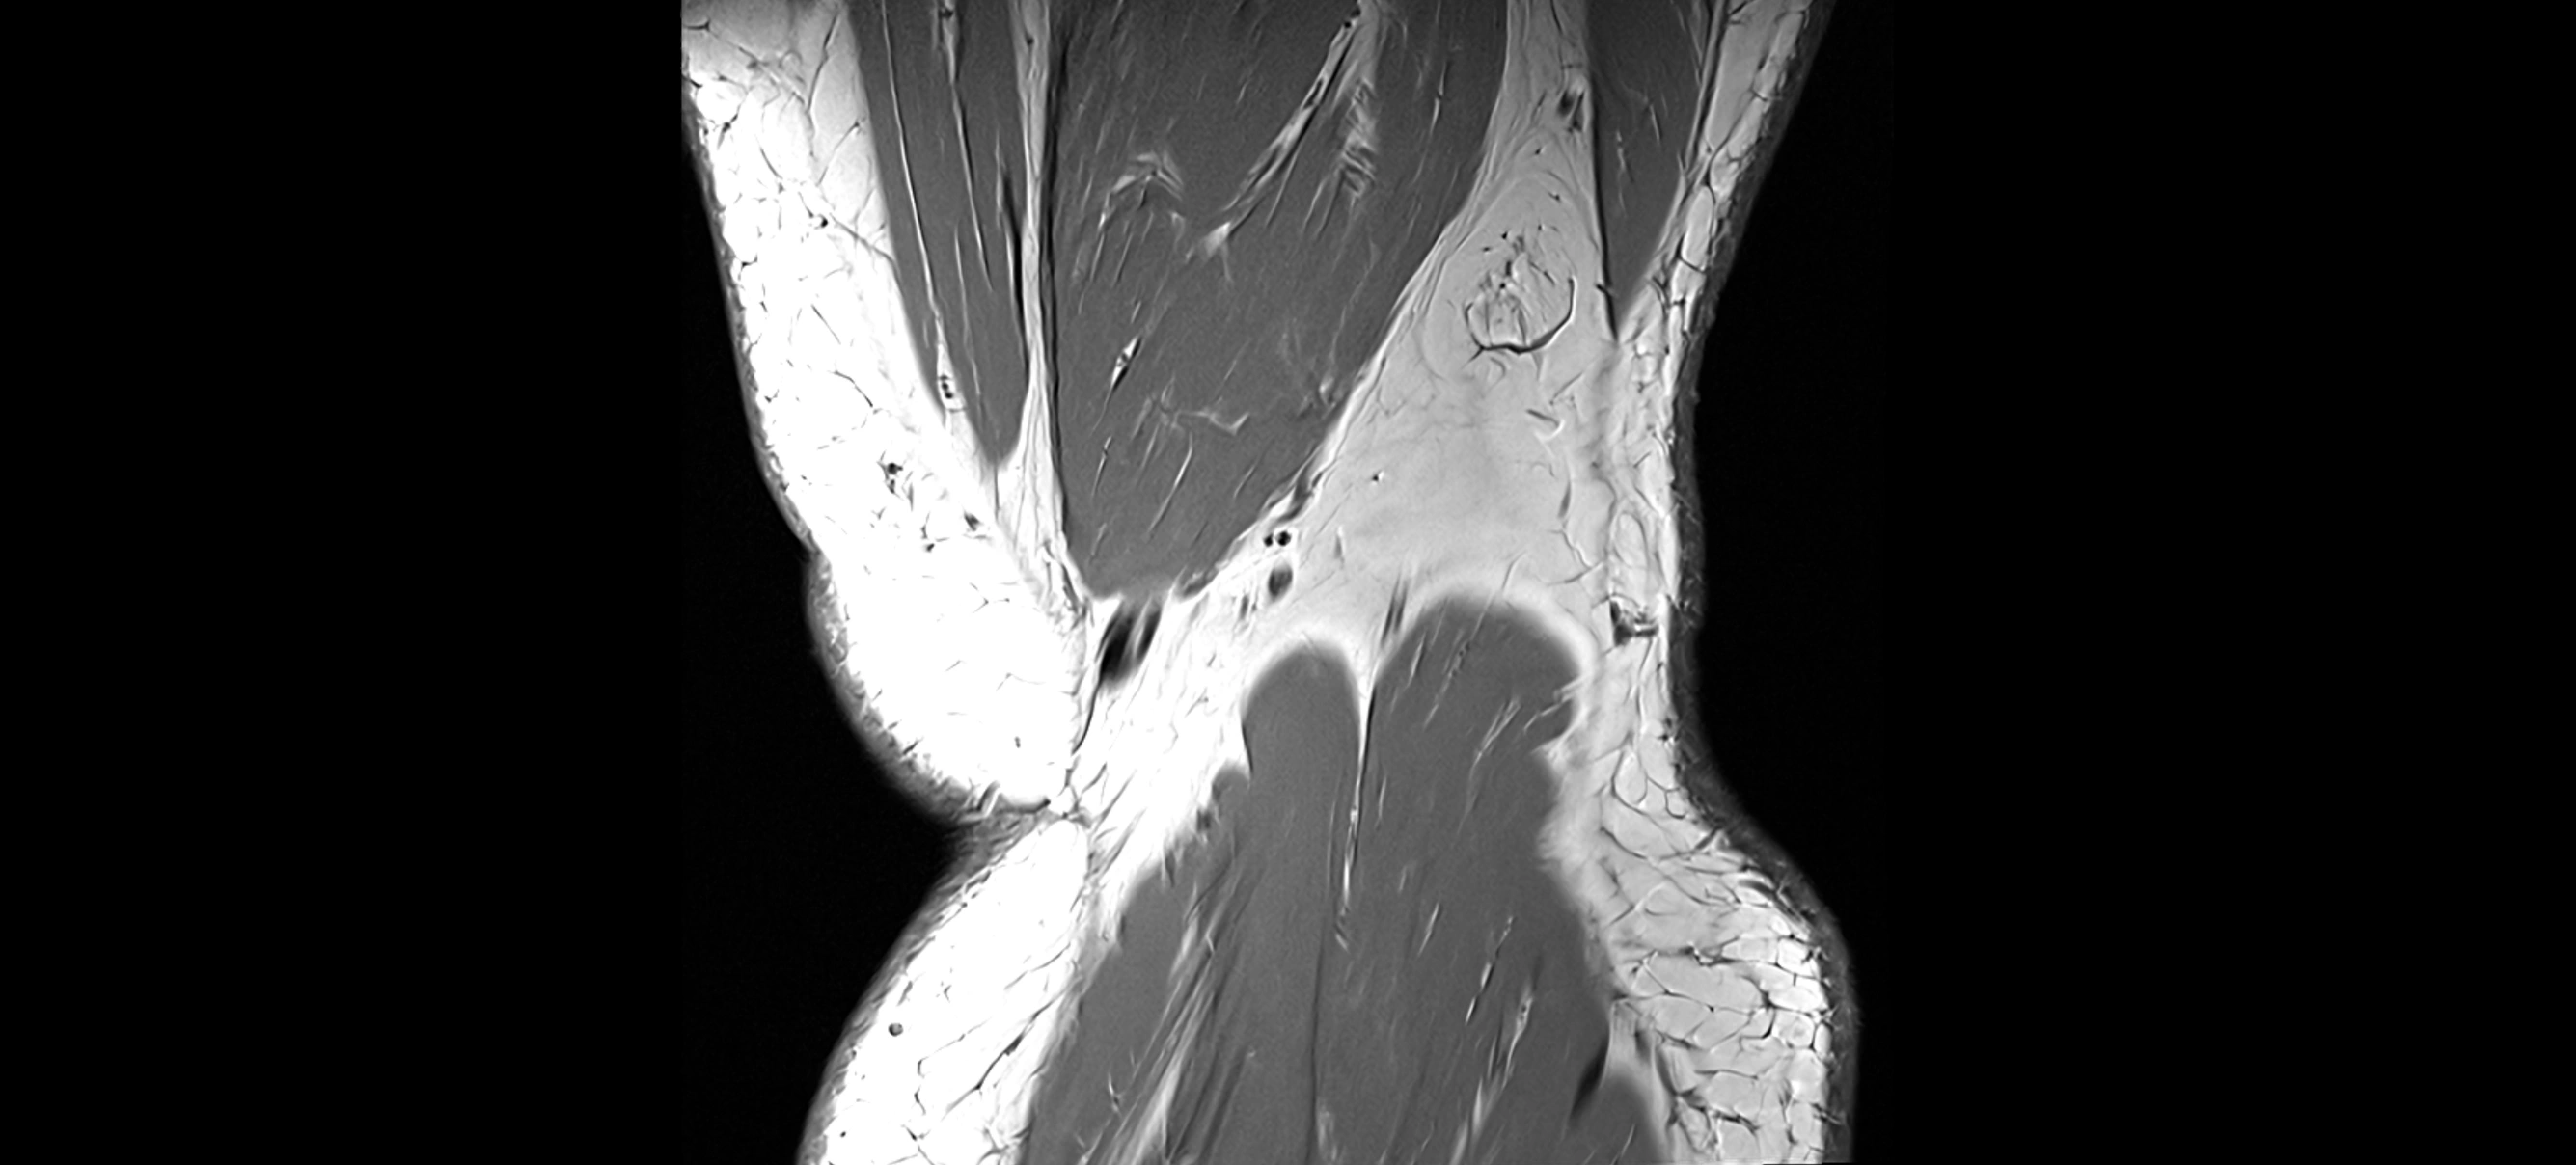

MRI images

image